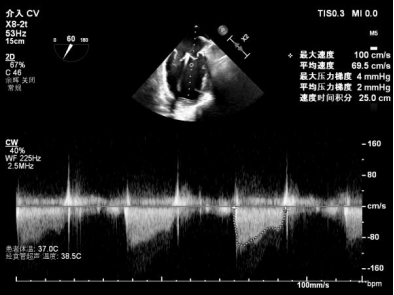

术前术后反流对比

【术后一周复查心超提示】二尖瓣钳夹术后,二尖瓣反流(轻度),夹合器固定,瓣口呈双孔结构,内外侧孔分别见微量反流,反流束VC分别 0.15cm、0.18cm,估测有效瓣口面积约2.5c㎡,舒张期瓣口前向最大血流速度 1.2m/s,平均压差3mmHg,左室射血分数(EF)值提升至35%,心功能显著改善。目前患者已顺利康复出院。